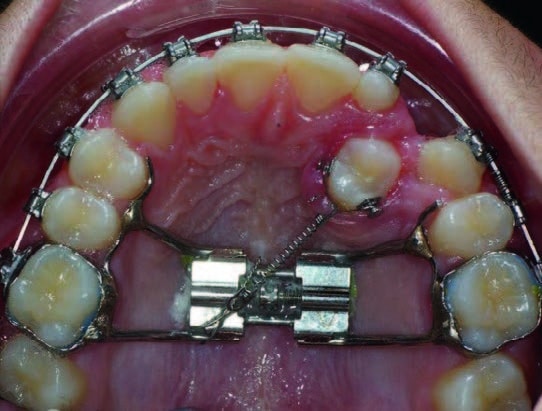

Chez cette patiente, une disjonction est nécessaire. Un disjoncteur maxillaire est mis en place et servira d’ancrage palatin pour rétablir la transposition ; (Fig.10).

Un mois après la fin de la disjonction, deux boutons sont collés en mésial et distal de 24 et la relient au disjoncteur par l’intermédiaire d’une chaînette élastomérique qui la tracte en direction disto-palatine. Le disjoncteur, maintenu pour stabiliser l’expansion maxillaire, sert en même temps d’ancrage pour le déplacement palatin de la prémolaire.

La traction peut aussi être réalisée par un ressort NiTi en traction qui est fixé sur le disjoncteur par l’intermédiaire d’une ligature métallique ; (Fig.11 et 12).